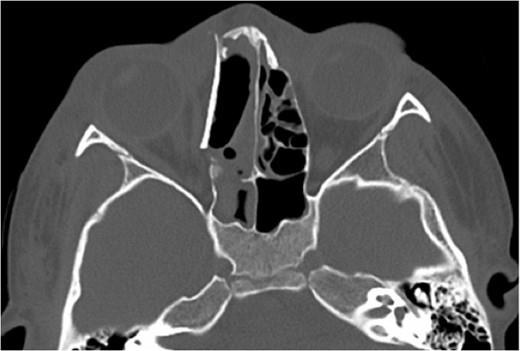

A 6-year-old boy with a background of asthma presented to a tertiary paediatric unit in May 2016 with a 3-day history of right eye pain, proptosis and erythema under the care of the ENT team. A provisional diagnosis of a periorbital cellulitis was made secondary to ethmoid sinusitis and management with intravenous antibiotics (ceftriaxone), intranasal steroids, saline douches and topical oxyxlometazoline was initiated. Ophthalmological assessment demonstrated normal colour vision, acuity and light reflexes bilaterally but also proptosis-related ophthalmoplegia. Computed tomography (CT) imaging of the orbits and paranasal sinuses demonstrated complete opacification of the right-sided paranasal sinuses and compromise of the right frontal and ostiomeatal unit. In addition there was an expansile abnormality centred on the ethmoidal labyrinth with bony remodelling of the lamina papyracea and a subperiosteal collection adjacent to the medial orbital wall (Figs 1 and 2). The most likely diagnosis was felt to be an infective process with mucopyocele formation complicated by a subperisoteal post-septal collection. An MRI scan with gadolinium of the orbits and sinuses confirmed the unilateral pattern of sinus opacification within the right frontal, ethmoids and maxillary sinus. The lesion demonstrated multiple fluid–fluid levels and peripheral enhancement (Figs 3 and 4). The patient was treated by endoscopic drainage of the lesion, which revealed only blood. He initially had some improvement of his proptosis but recurred within a few days and so further, more extensive endoscopic debridement was performed.

Axial T2 weighted sequence demonstrating the presence of multiple fluid filled levels (short white arrow) within the expansile lesion and smaller cyst present within the larger cyst (long white arrow).

At this point the MRI was reviewed and the possibility of an ABC was raised. This was due to the presence of fluid–fluid levels, cyst within a cyst appearance and lack of restricted diffusion within the sinonasal contents and material drained at the time of the first endoscopic procedure. He was discharged home on oral co-amoxiclav, and topical betamethasone nose drops.